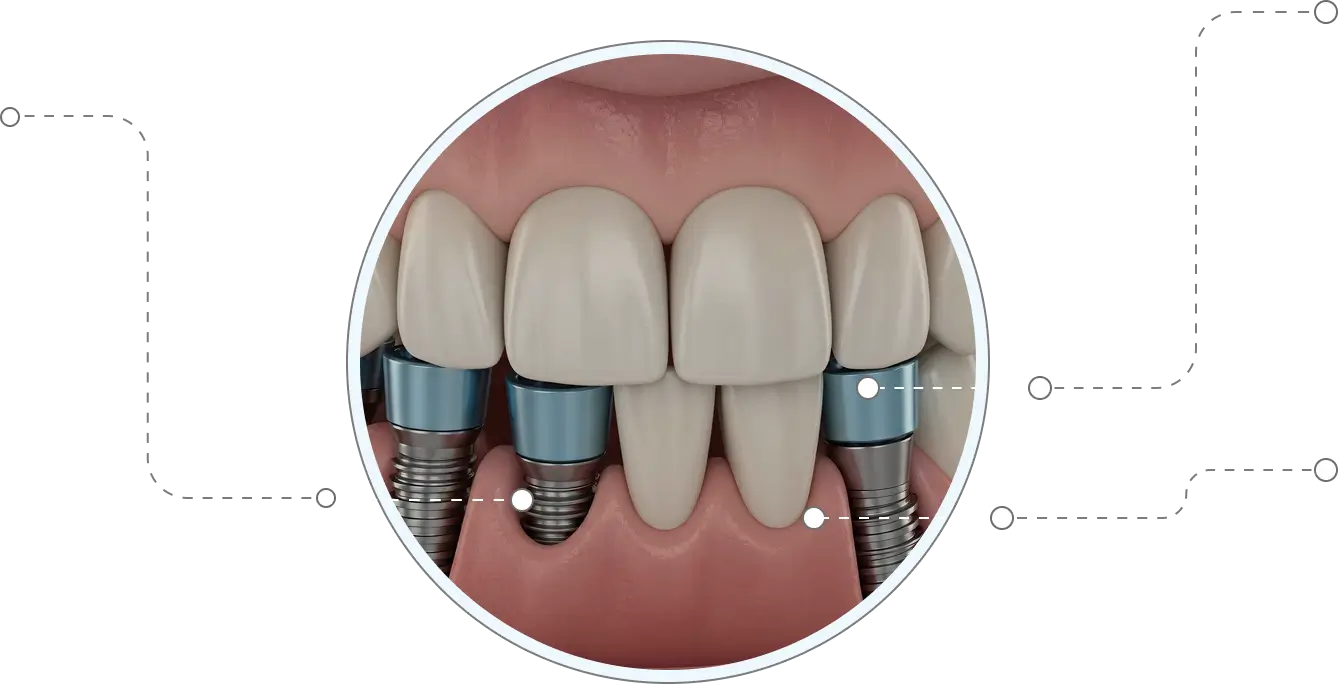

Our advanced Multiple Tooth Implants on the other hand are strong, durable and require only 2 implants to fix the replacement teeth into your natural denture. Traditional bridge comes with annoying metal clasps where as our implants have no such additional fixtures.

Multiple teeth Dental implants provide several advantages over other teeth replacement options. In addition to looking and functioning like natural teeth, implant-supported bridges replace teeth without support from adjacent natural teeth.

Independent Support

Our team of experts will develop custom fabricated crowns and are placed over the abutments and will function like a real tooth. You don’t have to worry about the future bone loss or difficulty in chewing your favorite food.